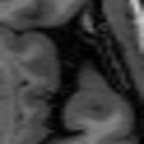

Sparsity Ikzsubscriptsuperscript𝐼𝑧absent𝑘I^{z}_{\downarrow k} LI 2D CNN 3D CNN Ours GT Ikz+1subscriptsuperscript𝐼𝑧1absent𝑘I^{z+1}_{\downarrow k}

4 Refer to caption Refer to caption Refer to caption Refer to caption Refer to caption Refer to caption Refer to caption

Refer to caption Refer to caption (a) 27.37/0.8465 Refer to caption (b) 32.34/0.9441 Refer to caption (c) 32.72/0.9436 Refer to caption (d) 34.11/0.9607 Refer to caption (e) PSNR(dB)/SSIM Refer to caption

8 Refer to caption Refer to caption Refer to caption Refer to caption Refer to caption Refer to caption Refer to caption

Refer to caption Refer to caption (f) 25.51/0.7681 Refer to caption (g) 28.29/0.8205 Refer to caption (h) 29.51/0.8824 Refer to caption (i) 31.87/0.9249 Refer to caption (j) PSNR(dB)/SSIM Refer to caption

Figure 5: Visual comparisons of slice interpolation approaches. For 4x sparsity, the second of three interpolated MR slices is presented. For 8x sparsity, the third of seven interpolated slices is presented.

5.3 Visual Comparisons

In Fig. 5, we present the observed slices Ikzsuperscriptsubscript𝐼absent𝑘𝑧I_{\downarrow k}^{z} and Ikz+1superscriptsubscript𝐼absent𝑘𝑧1I_{\downarrow k}^{z+1} along with the interpolated slices produced by different methods. Specifically we demonstrate the second of three interpolated MR slices for 4x sparsity, and the third of seven interpolated slices for 8x sparsity. We highlight the region where the anatomical structures significantly change compared to the observed slices Ikzsubscriptsuperscript𝐼𝑧absent𝑘I^{z}_{\downarrow k} and Ikz+1subscriptsuperscript𝐼𝑧1absent𝑘I^{z+1}_{\downarrow k}. We observe that although 2D CNN has comparable performance in terms of PSNR and SSIM, it tends to produce false anatomical structures in the zoomed regions. 3D CNN is able to resolve more accurate details. However, the improvement is quite limited, which we attribute to the fact that 3D CNN requires more training MR volumes in order to generalize and has smaller receptive field due to patch-based training. Our method benefits from the large receptive field of 2D CNN and two-view fusion, which not only produces sharper images, but also correctly estimates brain anatomy. The sharp and accurate estimation is crucial in clinical applications such as diagnosing Alzheimer’s Disease by brain volume estimation.